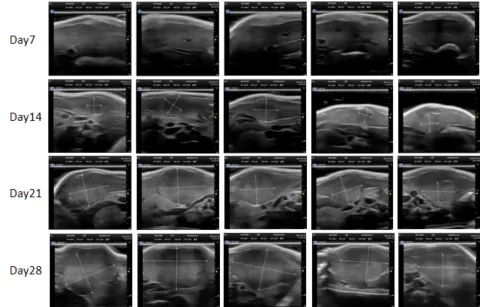

PDX Model (Growth Curve)

部分不朽情缘mg官网PDX原位模型展示